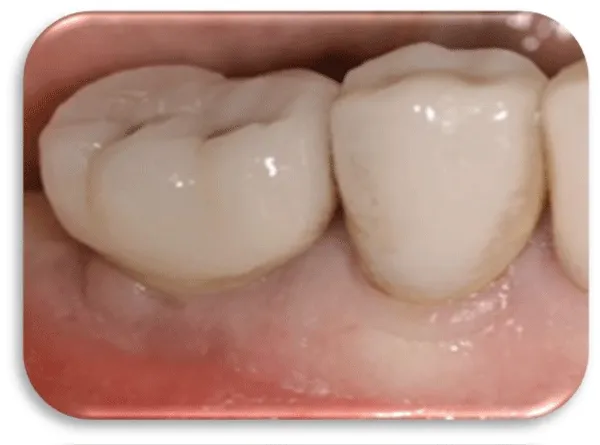

Different treatment strategies were performed in order to remove peri-implantitis. Provided treatment include: debridement of bone tissue, use of bone grafts from known biocompatible grafting materials, i.e. BioOS, disinfection of the surface of the dental implant. After 12 months, another radiography record was made, where ceramic crowns over the implants were seen and there was no longer peri-implantitis (Figure 20) [19,20].